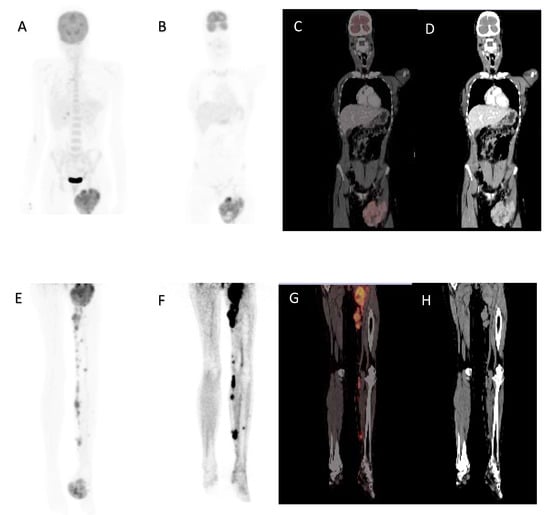

Figure 4.

A 32-year-old female, acral lentiginous melanoma resected from the left foot, presented with a recurrence and nodal metastases. Maximal intensity projection image (A), coronal 18F-FDG PET (B), fused (C) and CT (D) images demonstrating large inguinal node metastases. Maximal intensity projection image (E), Coronal 18F-FDG PET of lower limbs (F), fused (G) and CT (H) images demonstrating left foot primary with subcutaneous and nodal metastases in the left leg. MTV 126.73 cm3, TLG 567.75, SUVmax 10.78, whole-body MTV 635.48 cm3 and whole-body TLG 9964.33. Overall survival was 8 months.